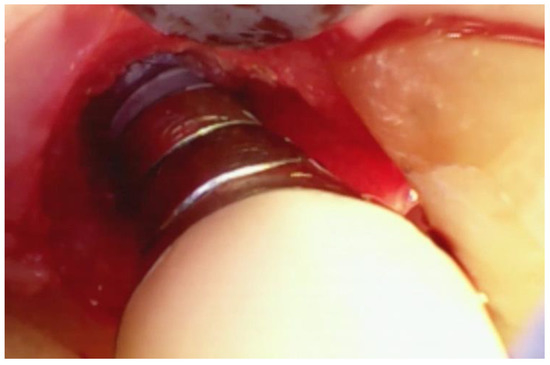

Figure 3. The split-thickness incisions at the base of the papilla (P in Figure 2) are designed to leave the periosteium intact. A periosteal elevator should not be used.

A sulcular incision (S in Figure 2) is made on the lingual aspect of the teeth on either side of the area of bone loss. When these incisions are made, the blade is placed against the root surface and inserted to the base of the defect. No tissue is removed with this incision. Unlike more traditional surgical approaches where the sulcus lining is removed or a “collar of tissue” is removed, the goal with VMIS incisions is to sever the granulation tissue only and to leave the rest of the tissue intact. Following the placement of the sulcular incisions, a connecting incision is made at the base of the papilla (P in Figure 2). This incision is made only to the crest of the bone. The goal is to retain as much of the periosteium on the bone as possible. Depending on the anatomy of the area, this may be the full extent of incisions that is necessary. If there is inadequate room to place the soft tissue retractor of the videoscope or if the bony defect cannot be adequately visualized, the papillary incision (P) can be extended apically as a split-thickness incision (Figure 3). Under no circumstance should a periosteal elevator be used to gain space. A periosteal elevator will pull the periosteium from the bone, which will greatly diminish the blood supply to the periodontal tissue. The use of a periosteal elevator is associated with a greater recession than that observed when a split-thickness approach is used.